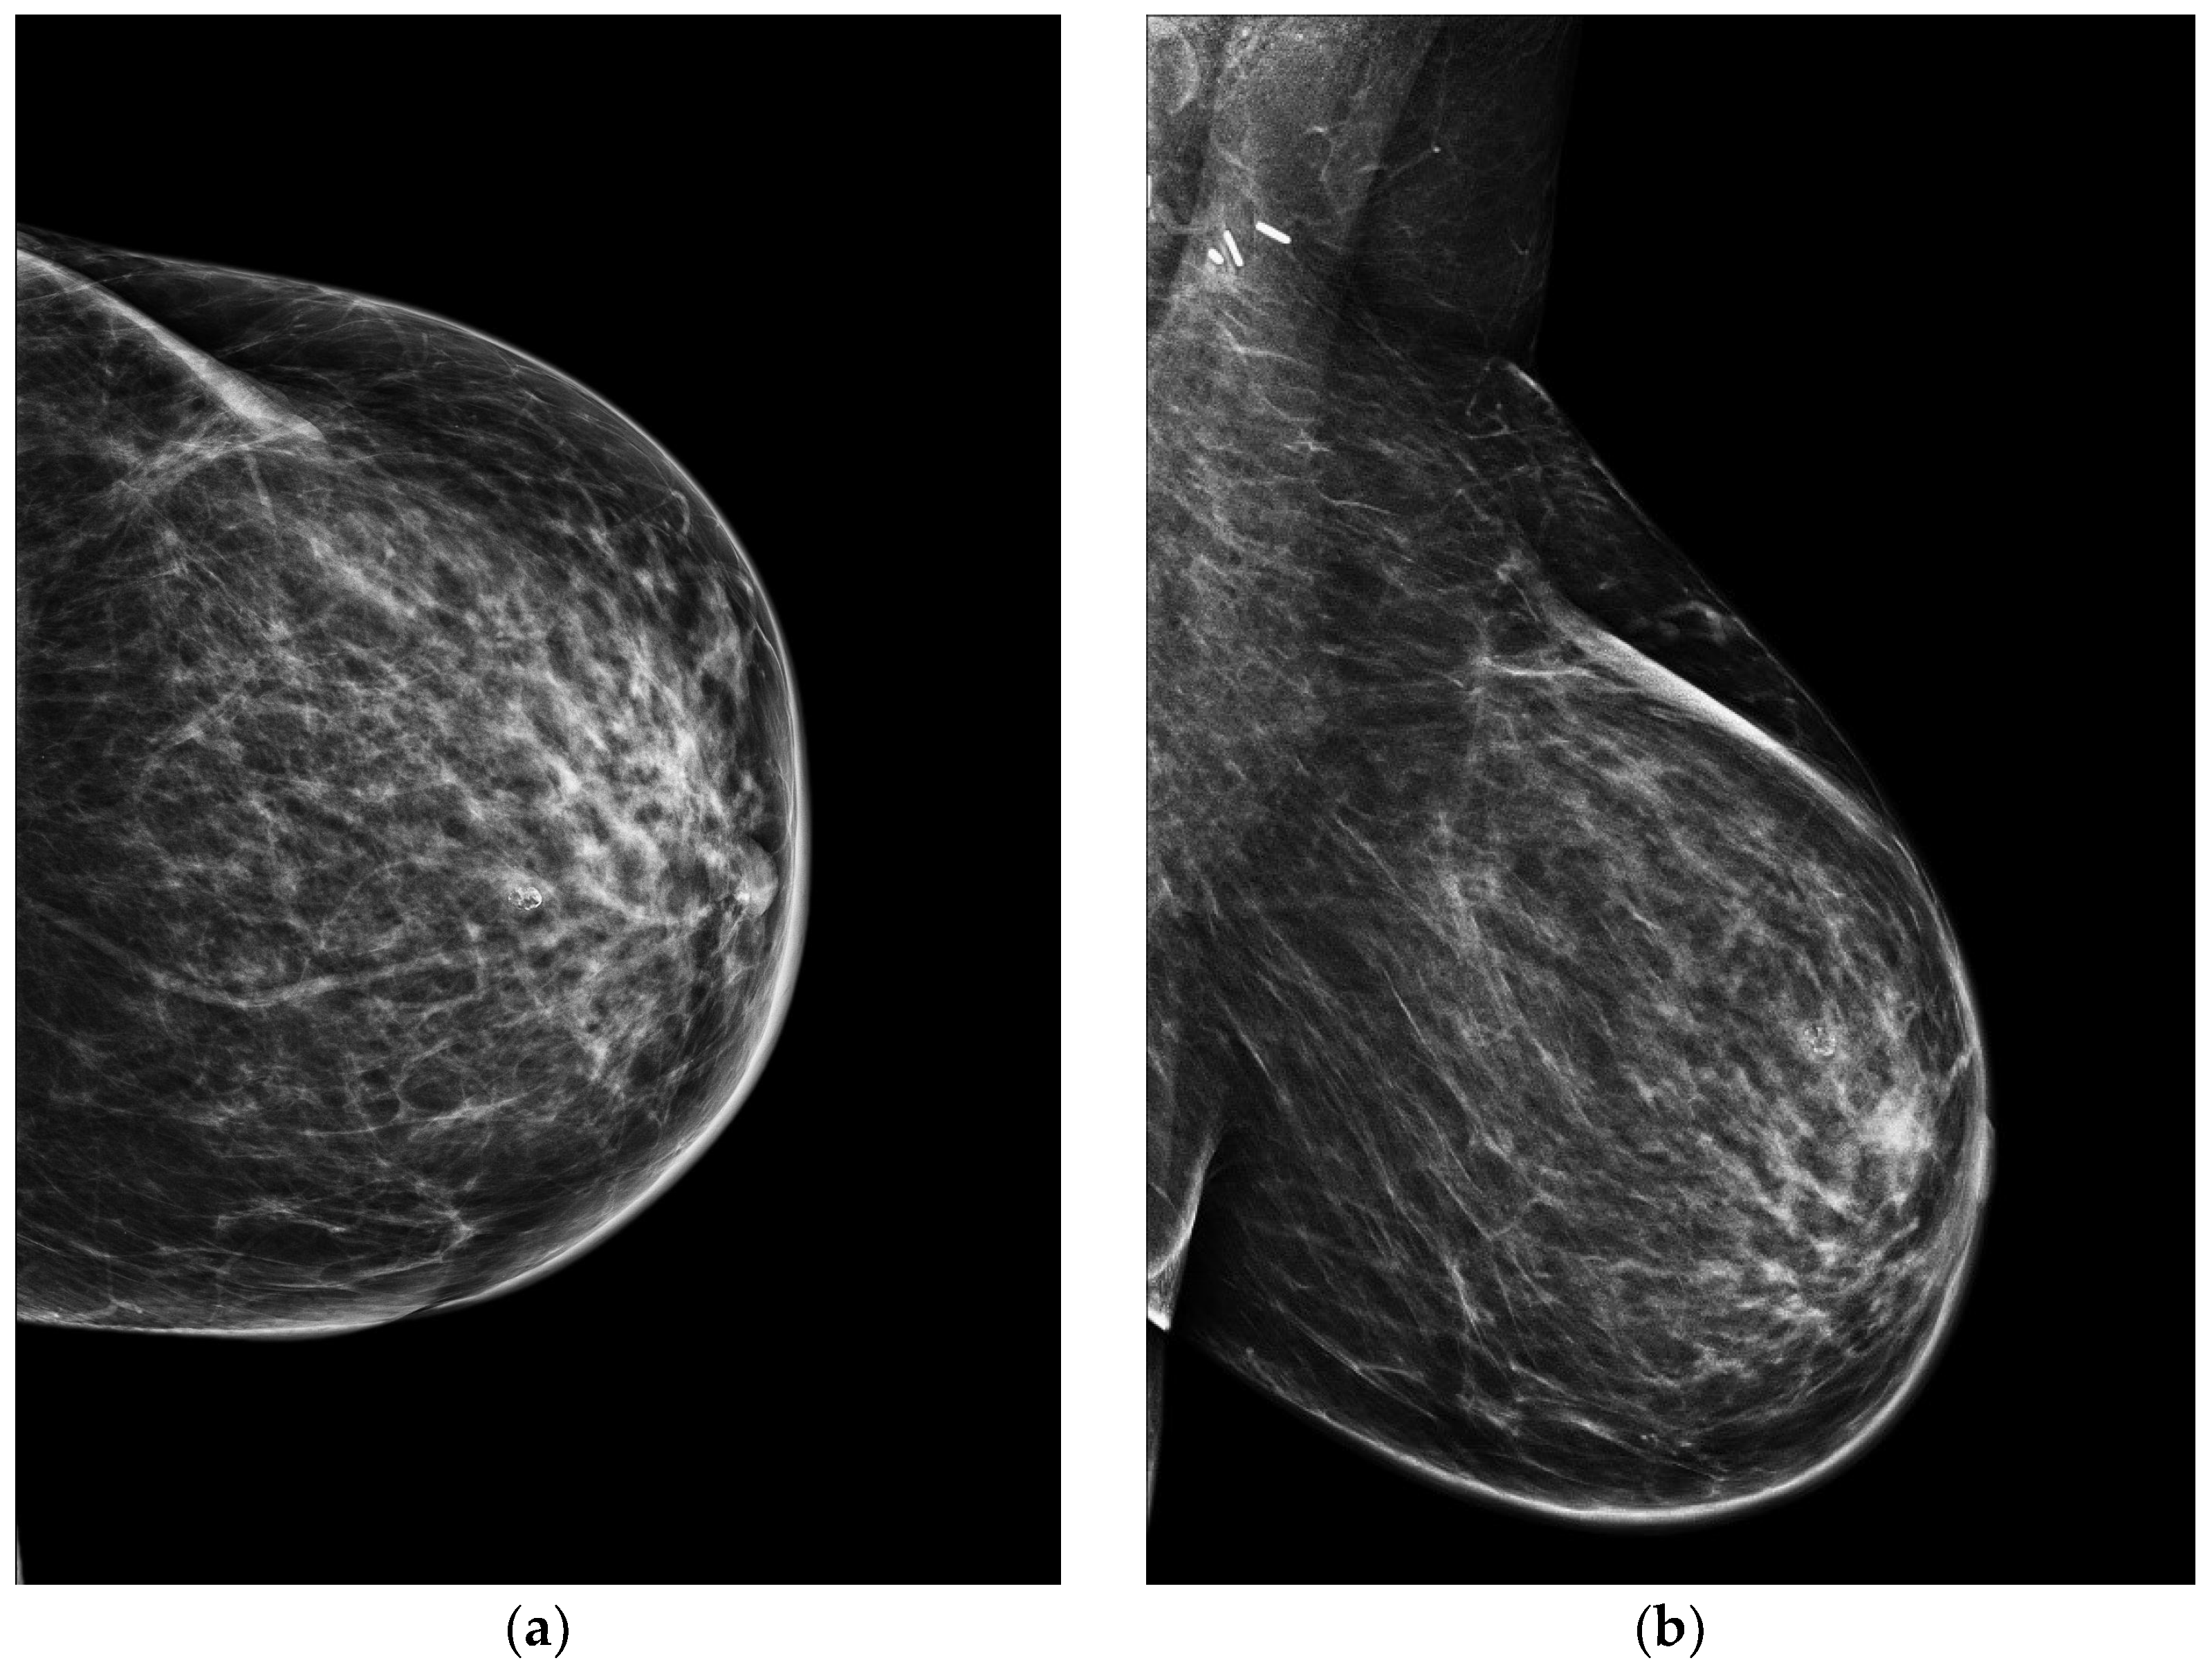

4.1. Mammography